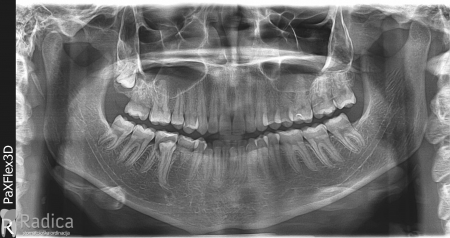

U ovom slučaju je 41.godinu starom pacijentu počeo nicati impaktirani desni gornji očnjak pri čemu je ugrozio lateralni sjekutić. Pacijentu je stavljen fiksni aparat te je zub smješten u luk. Kako je pacijent odustao od postave aparata u donjoj čeljusti na kraju nije dobivena zadovoljavajuća okluzija na što je upozoren.